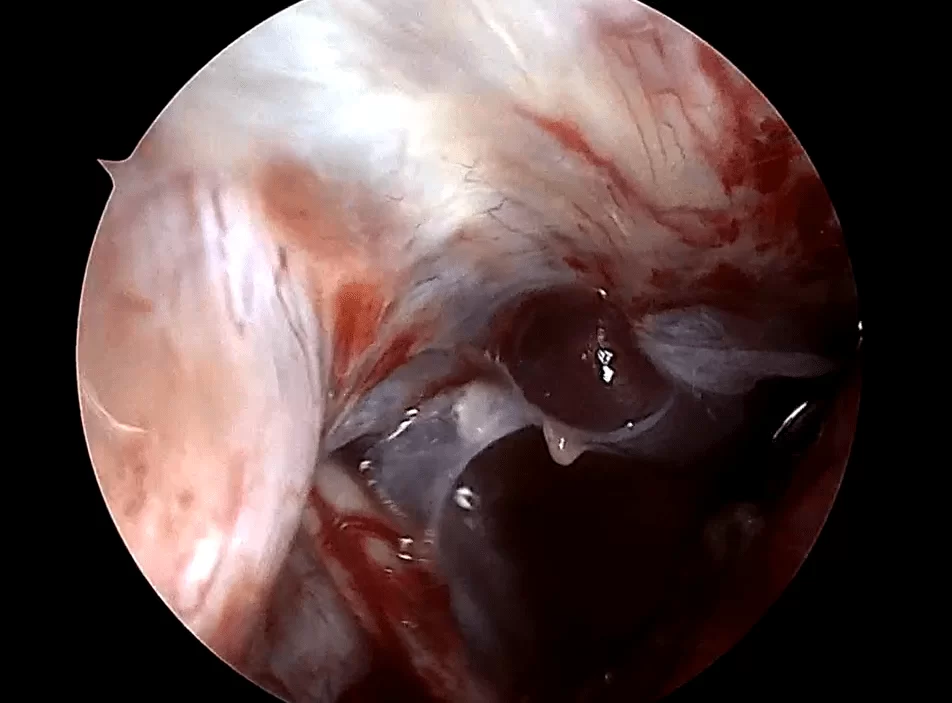

Η μίνι οπισθομαστοειδική κρανιοτομία χρησιμοποιεί ένα μικρό άνοιγμα στο οστό πίσω από το αυτί (Εικόνα 3) για να προσπελάσει ακουστικά νευρινώματα, μηνιγγιώματα, επιδερμοειδείς όγκους και όγκους της παρεγκεφαλίδας όπως αιμαγγειοβλαστώματα και μεταστατικούς όγκους.

Είναι επίσης η κύρια προσέγγιση για μικροαγγειακή αποσυμπίεση των κρανιακών νεύρων (για νευραλγία τριδύμου ή για σπασμό του ημιπροσώπου). Συχνά συνδυάζεται με τη χρήση του ενδοσκοπίου (Εικόνα 4).